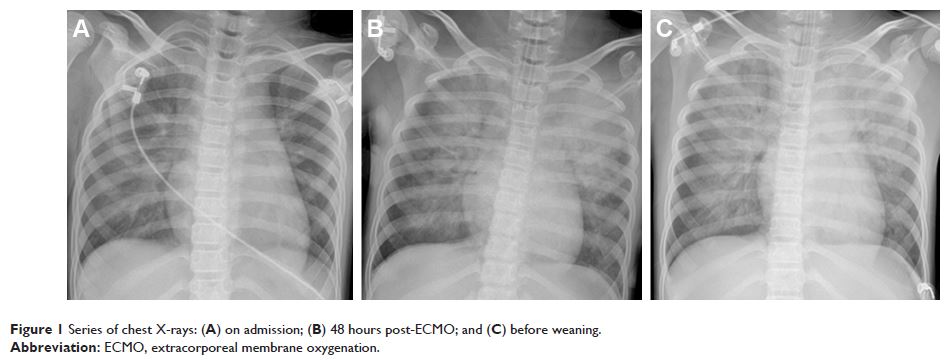

Case Report

- 作者:Ya-Ting Li, Li-Fen Yang, Zhuang-Gui Chen, Li Pan, Meng-Qi Duan, Yan Hu, Cheng-bin Zhou, Yu-Xiong Guo

- 期刊:Therapeutics and Clinical Risk Management